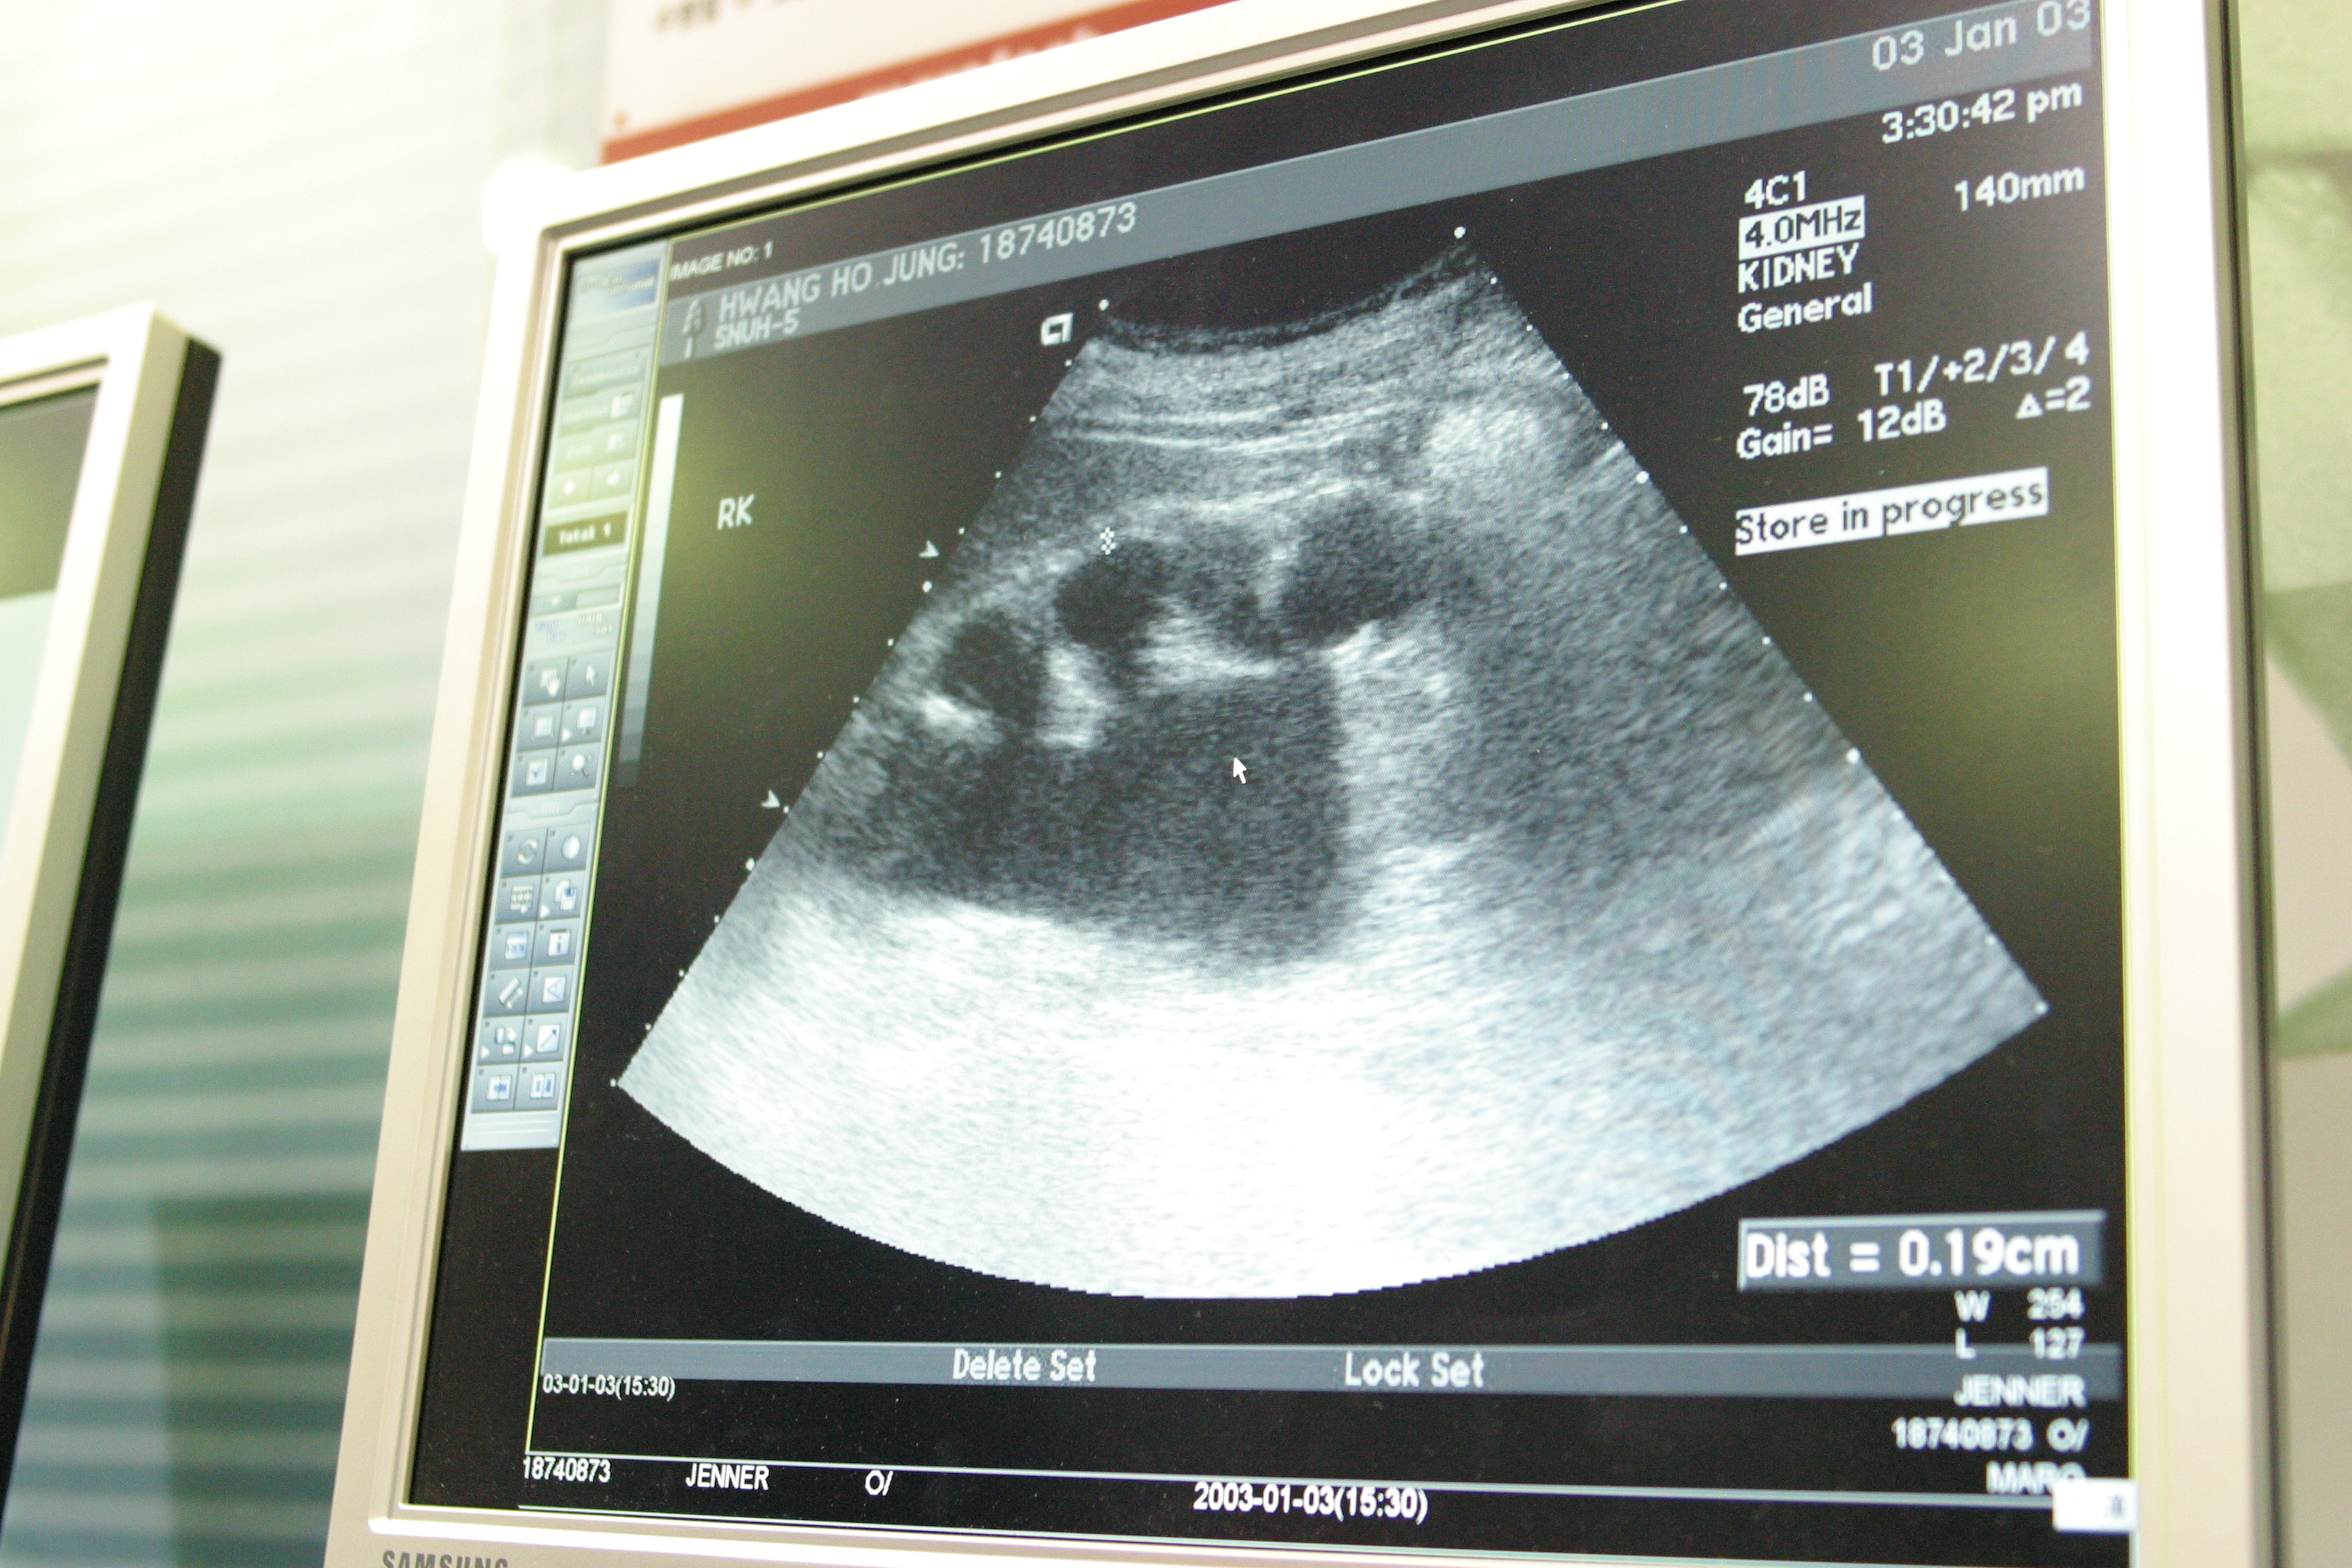

관내 유일한 외래 산부인과의 필수 의료장비인 초음파기 태아감시장치는 도입된 지 10년이 지나 이미 장비의 수명이 다했습니다.

수명이 다한 낡은 장비는 태아의 미세한 기형이나 이상 징후를 발견하기 어렵습니다.

심지어 센서 감도가 낮아 산모의 맥박태아의 심박동조차 제대로 구분하지 못하는 실정입니다.

▲ 건양대학교부여병원의 노후 된 장비 모습들 (좌)초음파기 (우)태아감시장치 ©부여군

⚠️ 초음파기 : 2015년 도입되어 10년 넘게 사용 중입니다.

해상도가 떨어져 미세한 구조적 결함을 식별하기가 어렵고 초기 병변 발견이 힘든 상황입니다.

산전 관리의 핵심은 고성능 초음파를 통해 태아의 기형이나 발달 이상을 조기에 발견하는 것입니다.

하지만 현재 부여군이 보유한 장비들은 이미 장비 수명의 한계치를 훌쩍 초과했습니다.

낮은 해상도로 인해 태아의 상태를 정확히 판독하기 어렵다 보니, 장비에 대한 불신은 커져만 갑니다.